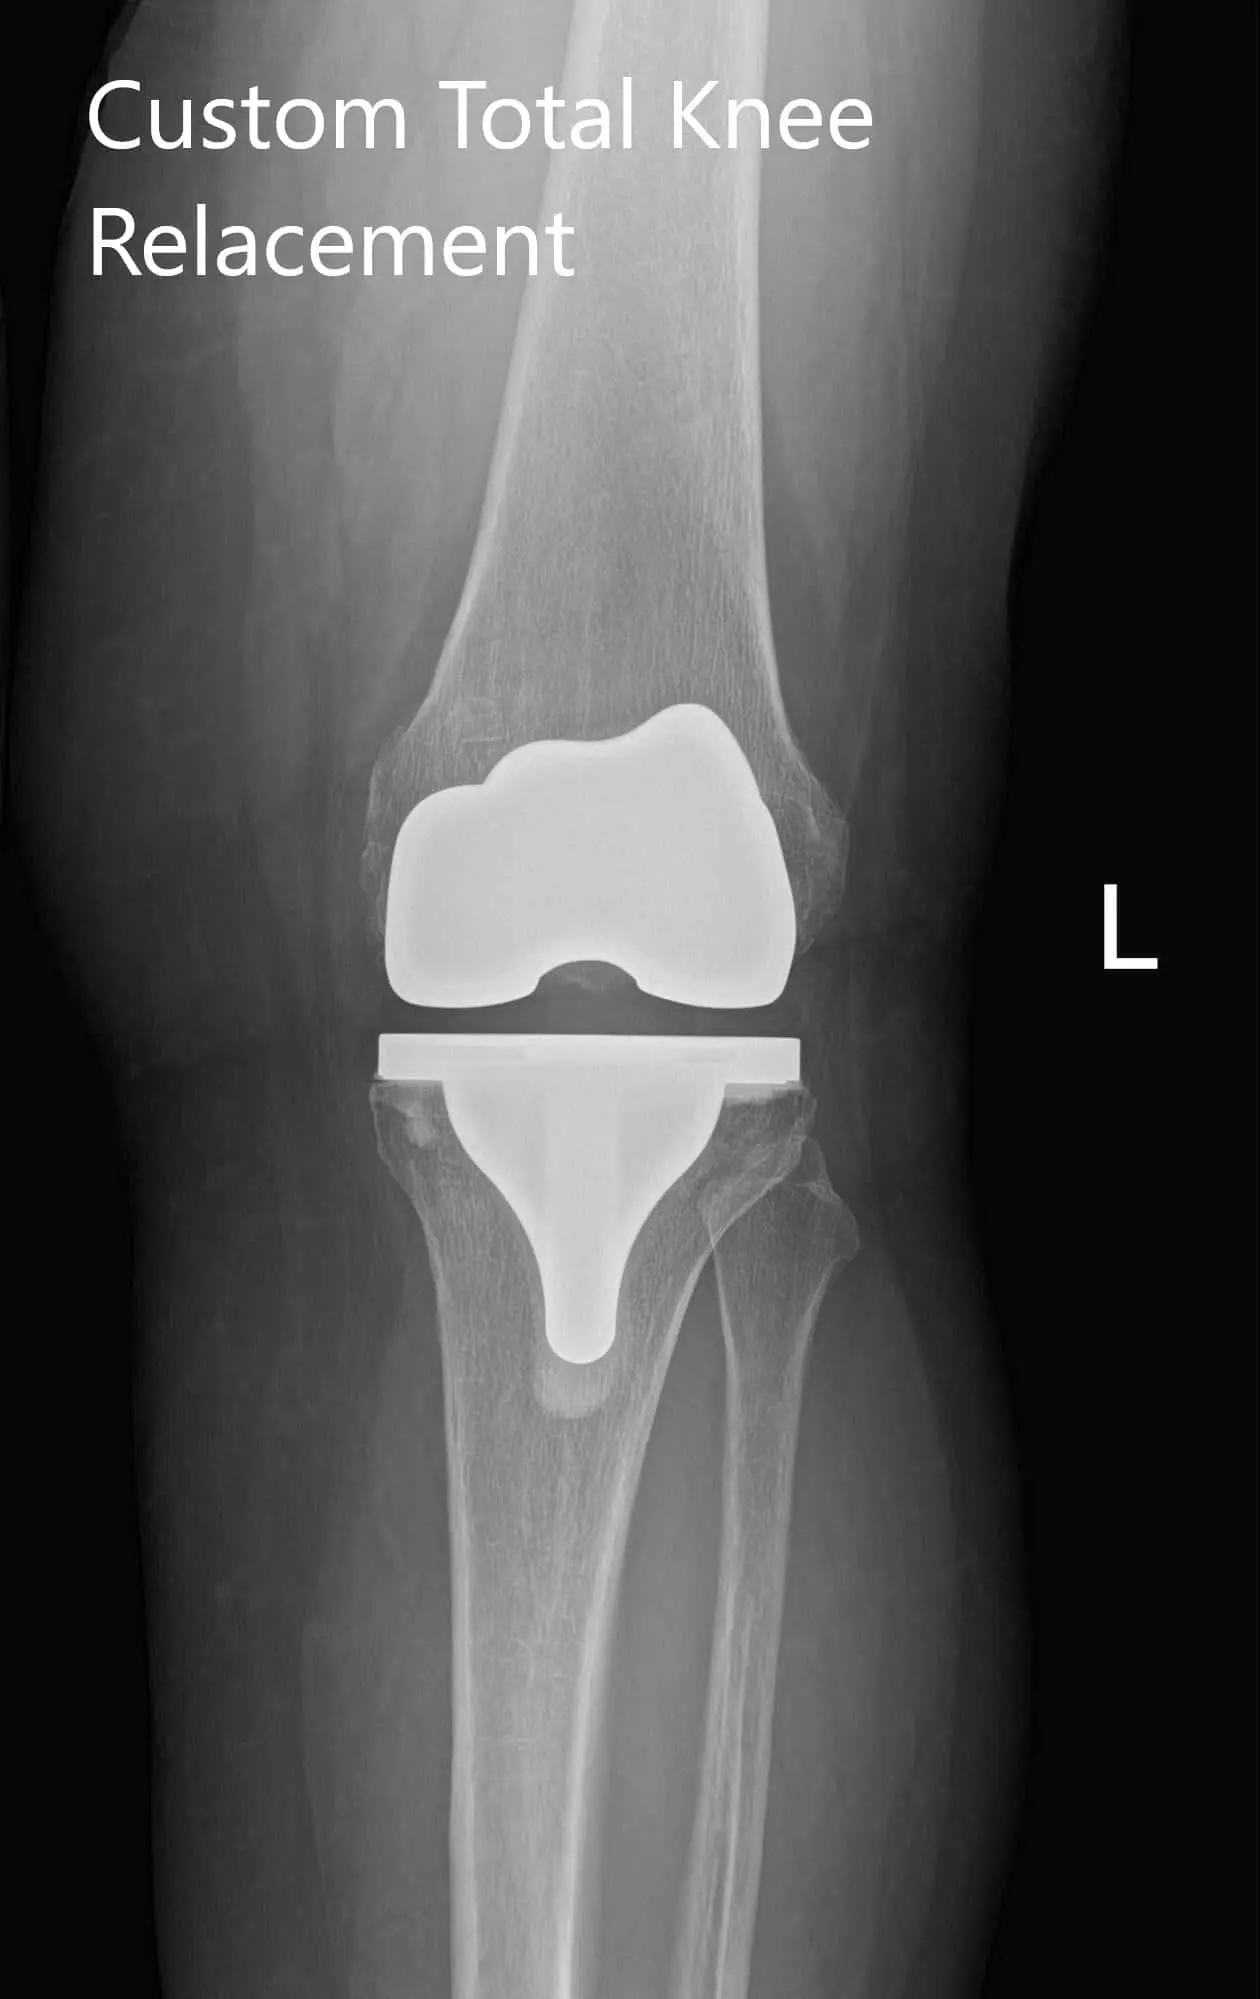

Post Operative X-Ray of the left knee showing AP and lateral viewPost Operative X-Ray of the left knee showing AP and lateral view - img 2

Post Operative X-Ray of the left knee showing AP and lateral view